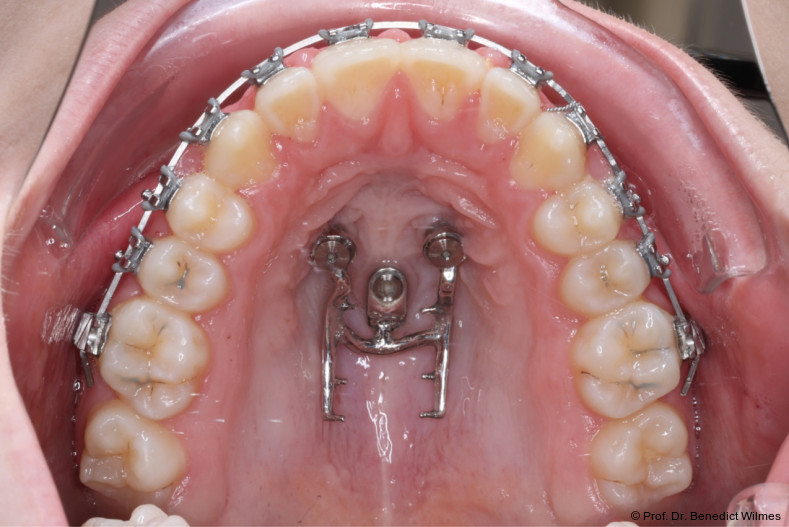

Klinisches Prozedere

Die initiale Behandlung erfolgte mit einer CAD/CAM Hybrid Hyrax zur Expansion des Oberkiefers, verankert an zwei paramedianen Miniimplantaten (Abb. 4, Benefit, 2,0 x 9,0 mm). Anstelle klassischer Molarenbänder wurden Shells (geklebte Kappen) verwendet, wodurch die beiden Schritte Separieren und Anpassen von Molarenbändern entfallen. Die Miniimplantate und die Apparatur wurden dank eines Inser­tionsguides in nur einer Sitzung eingesetzt.

Die Shells wurden mit lichthärtendem Kom­posit befestigt. Nach Expansion des Oberkiefers (Abb. 5a–f) erfolgte eine Retentionsphase von neun Monaten, in der die Hybrid Hyrax in situ belassen wurde.

Nach dieser Rentionszeit wurde die Hybrid Hyrax entfernt und ein Scan zur Herstellung der Molarenintrusionsapparatur (digitale Mause­falle) durchgeführt. Die beiden Miniimplantatköpfe lassen sie dabei sehr gut scannen, so­genannte Scan-Bodies sind in der Regel nicht mehr notwendig. Die digitale Mousetrap-­Appa­ratur besteht aus zwei Teilen (Abb. 6):